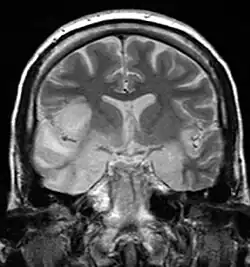

MRI scan image shows high signal in the temporal lobes and right inferior frontal gyrus in someone with herpes simplex encephalitis. | |